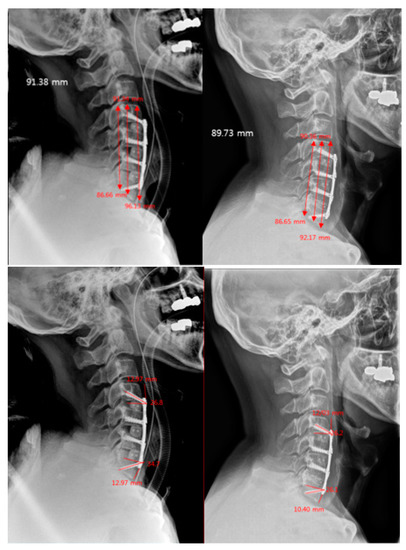

2.2. Evaluation of Radiologic Outcomes

- C2–7 Cervical Lordosis (CL): Cobb’s Method. This was measured by the angle formed by the perpendicular lines parallel to the inferior endplates of C2 and C7 [12].

- C2–7 Sagittal Vertical Axis (SVA): the distance between the C2 plumb line and the posterosuperior corner of C7 [12].

- Plate-to-Disc Distance: distance from the most proximal part and most distal part of the plate to the superior and inferior adjacent disc spaces, respectively [13].

- Screw Angles: angle between a line perpendicular to the plate and the direction of the screw [6].

- Subsidence: the vertical length from the superior endplate of the most superior vertebra to the inferior endplate of the most inferior vertebra [14].